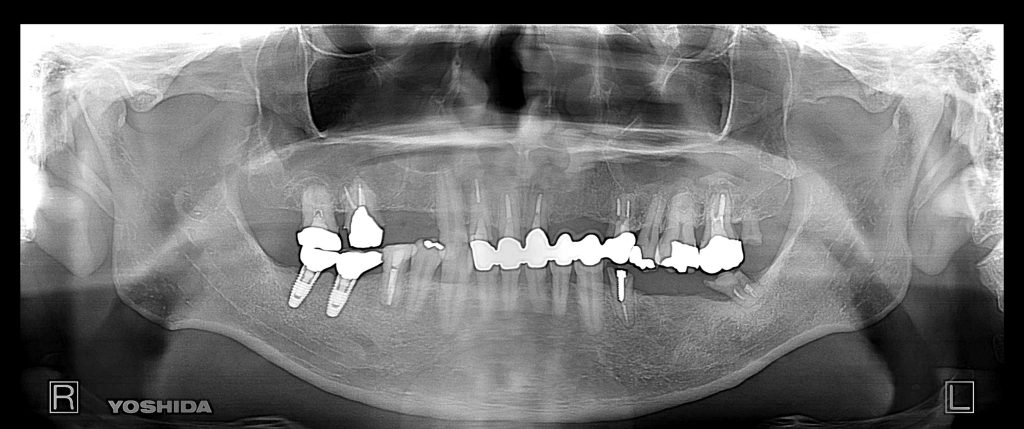

症例140代 男性 主訴 左右臼歯部欠損の為、奥歯で噛めない 前歯がグラつく

治療前

治療後

奥歯でしっかり噛めるようにインプラントを計画・提案。

前歯の長いブリッジは力学的に負担がある為、支えとなるインプラントを配置。

右上小・大臼歯部は、骨高不足の為、ソケットリフト(上顎洞洞底膜挙上術)を適用。

約5ヶ月間の治療期間を経て、全てジルコニアを装着し終了。

リスクとしては外科的侵襲がある。デメリットは、保険外診療の為、経済的負担がある。

費用 340万(税込)(オペ・仮歯・最終補綴物まで含む)